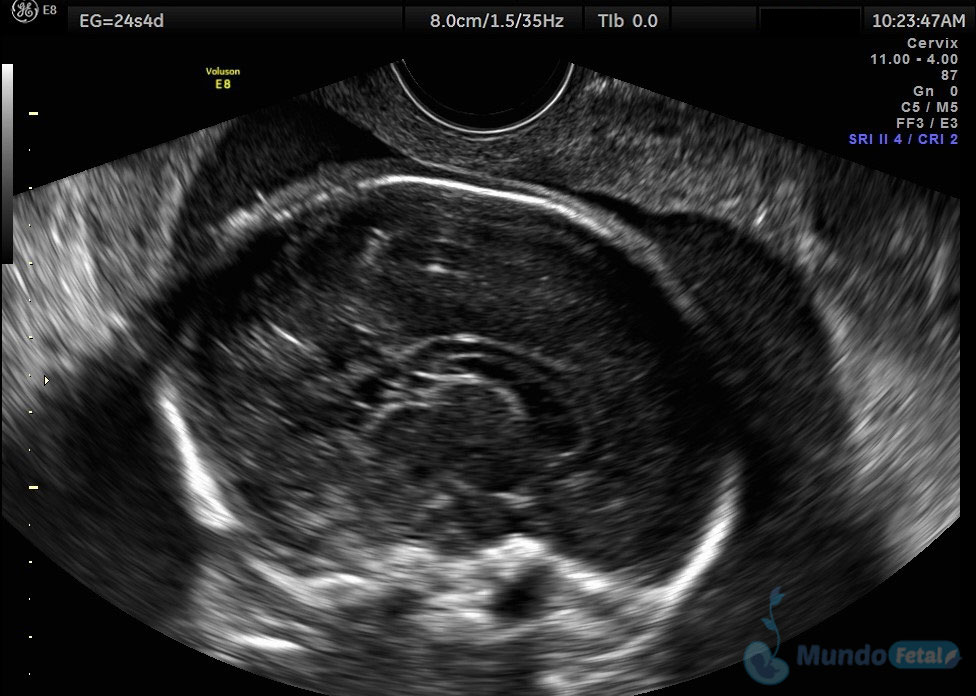

Ultrasonido 2do Trimestre 18-23 Semanas (Estructural o Anatómico)

Entre las 18 y 22 semanas, el feto ha desarrollado la mayoría de sus estructuras anatómicas, permitiéndonos valorar de manera detallada todos los órganos del bebe, descartando anomalías anatómicas fetales y datos de cromosomopatías. Prediciendo además preeclampsia (Doppler de arterias uterinas) y parto prematuro (por medio de la medición de la longitud del cérvix). En manos expertas, la detección de anomalías anatómicas supera el 80%.